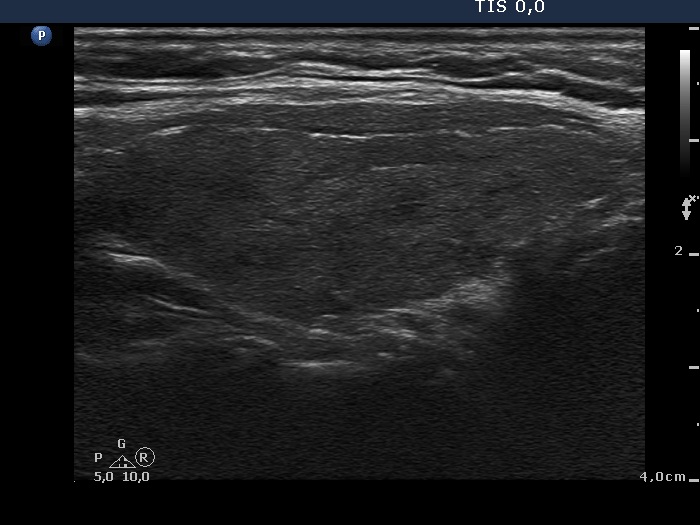

The borders of the nodule - case conp 060 (ultrasonographic picture 6)

Left lobe, longitudinal view.